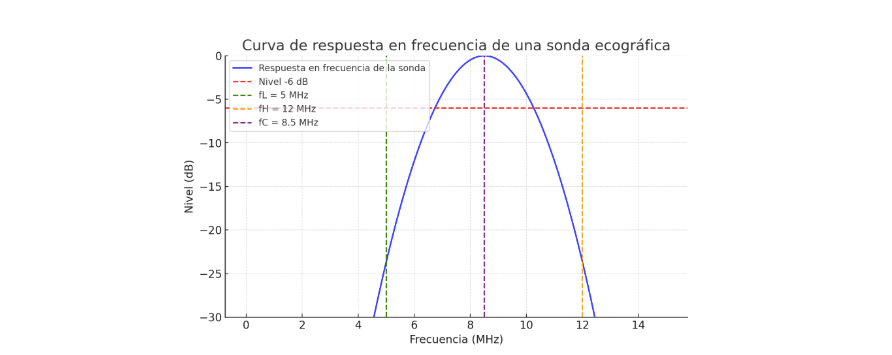

Clasificación ecográfica de Pedret y Balius (2020)

El sistema más detallado actualmente clasifica las lesiones del Tennis Leg según la localización y grado de afectación aponeurótica:

| Tipo | Descripción | Pronóstico |

|---|---|---|

| Tipo 1 | Lesión mioaponeurótica sin rotura de la aponeurosis | Rápida recuperación |

| Tipo 2A | Rotura < 50 % de la aponeurosis del gastrocnemio | Buena evolución |

| Tipo 2B | Rotura > 50 % con asincronía gastrocnemio-sóleo | Recuperación media |

| Tipo 3 | Lesión de la aponeurosis libre del gastrocnemio | Rehabilitación prolongada |

| Tipo 4 | Lesión mixta GA + FGA con retracción muscular | Peor pronóstico |